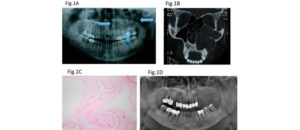

192 – Clasificación propuesta para los contactos interproximales de los molares primarios utilizando CBCT: Un estudio piloto

El «Área de contacto» es un término que se usa para denotar las alturas proximales del contorno de las superficies mesial y distal del diente.